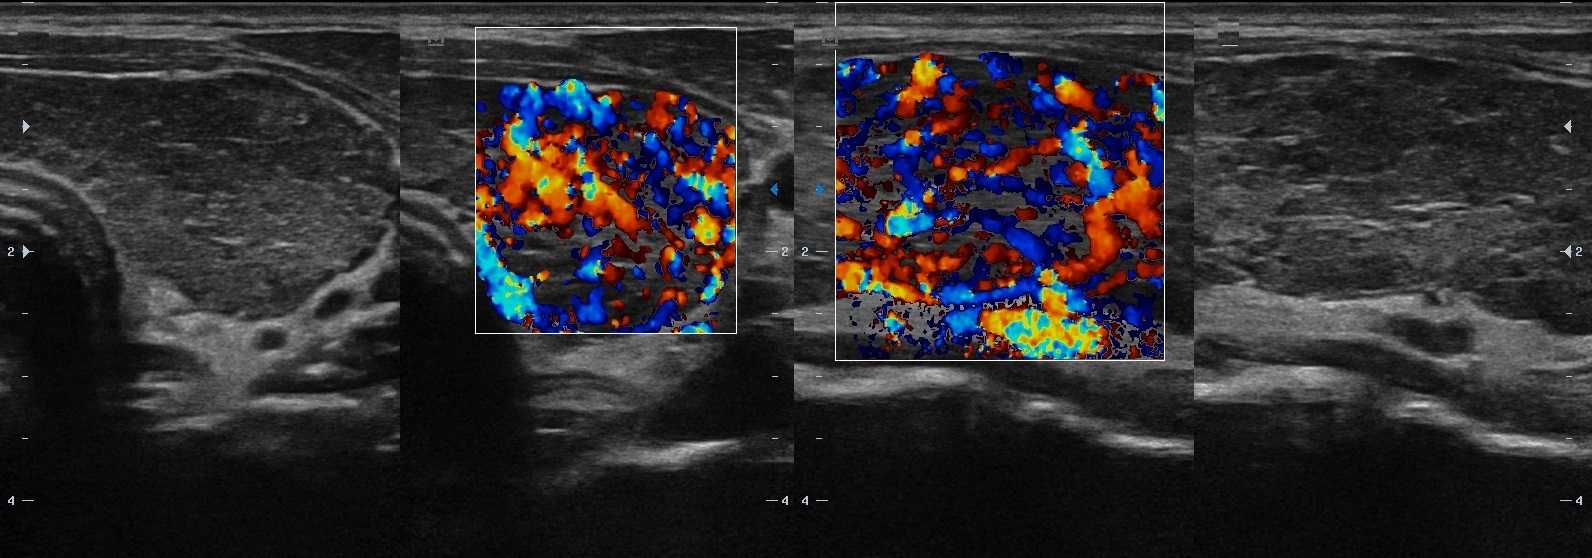

При аутоиммунном тиреоидите на УЗИ паренхима гипоэхогенная, грубонеоднородной за счет узелков (2-6 мм) разной эхогенности, неправильной формы. Очаги изоэхогенные к ткани слюнных желез пока не вовлечены в воспаление; в резко гипоэхогенных фокусах воспаление максимально выражено; в гиперэхогенных округлых или линейных структурах произошло замещение паренхимы на соединительную ткань. При тиреоидите Хашимото аномальная УЗ-картина сохраняется на протяжении всей жизни пациента. Подробнее смотри Аутоиммунная щитовидная железа на УЗИ (лекция на Диагностере).

Рисунок. Девочка 10-ти лет с эутиреозом и антитиреоидными антителами. На УЗИ щитовидная железа увеличена в 1,5 раза — 13 см3 (норма до 8,3 см3). На фоне неизмененной паренхимы определяются гипоэхогенные «змеи» (лимфоидная инфильтрация по ходу сосудов). Кровоток заметно усилен. Заключение: АИТ, гипертрофическая форма. Аналогично может начинаться диффузный токсический зоб.

Рисунок. Пациент с гипотиреозом и антитиреоидными антителами. На УЗИ щитовидная железа диффузно увеличена; контур волнистый; на фоне нормальной паренхимы в большом количестве гипоэхогенные очаги (3-5 мм) с четким контуром без «гало». Заключение: АИТ, гипертрофическая форма.

Рисунок. Пациент с гипертиреозом и антитиреоидными антителами. На УЗИ щитовидная железа диффузно увеличена; на фоне общего снижения эхогенности определяются гипоэхогенные включения (2-4 мм) и линейные гиперэхогенные структуры; кровоток заметно усилен. Заключение: АИТ, гипертрофическая форма.